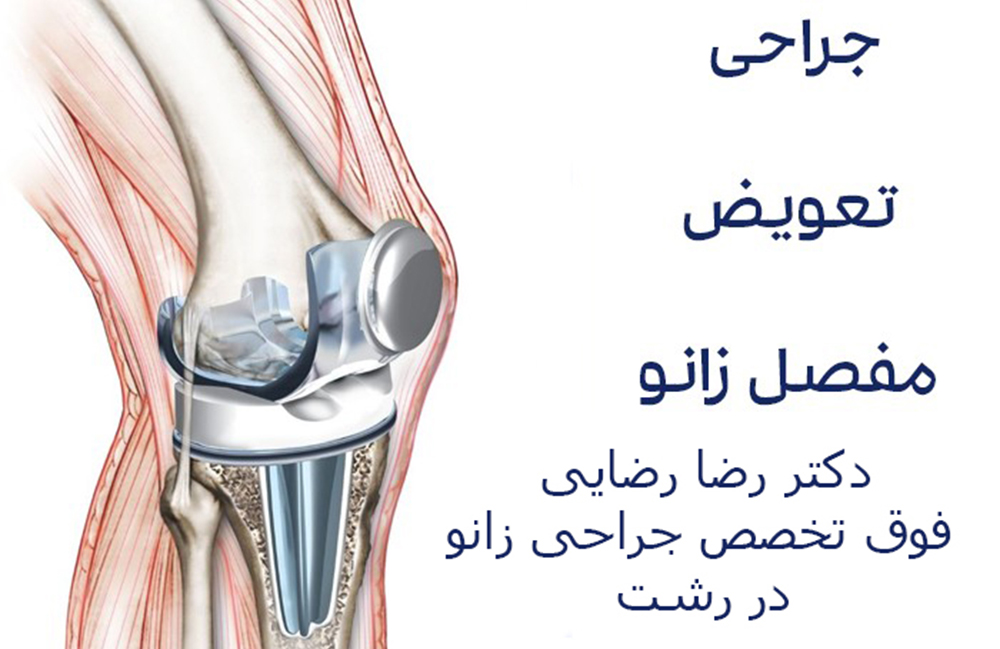

همچنین مقاله تعویض مفصل زانو را مطالعه کنید.